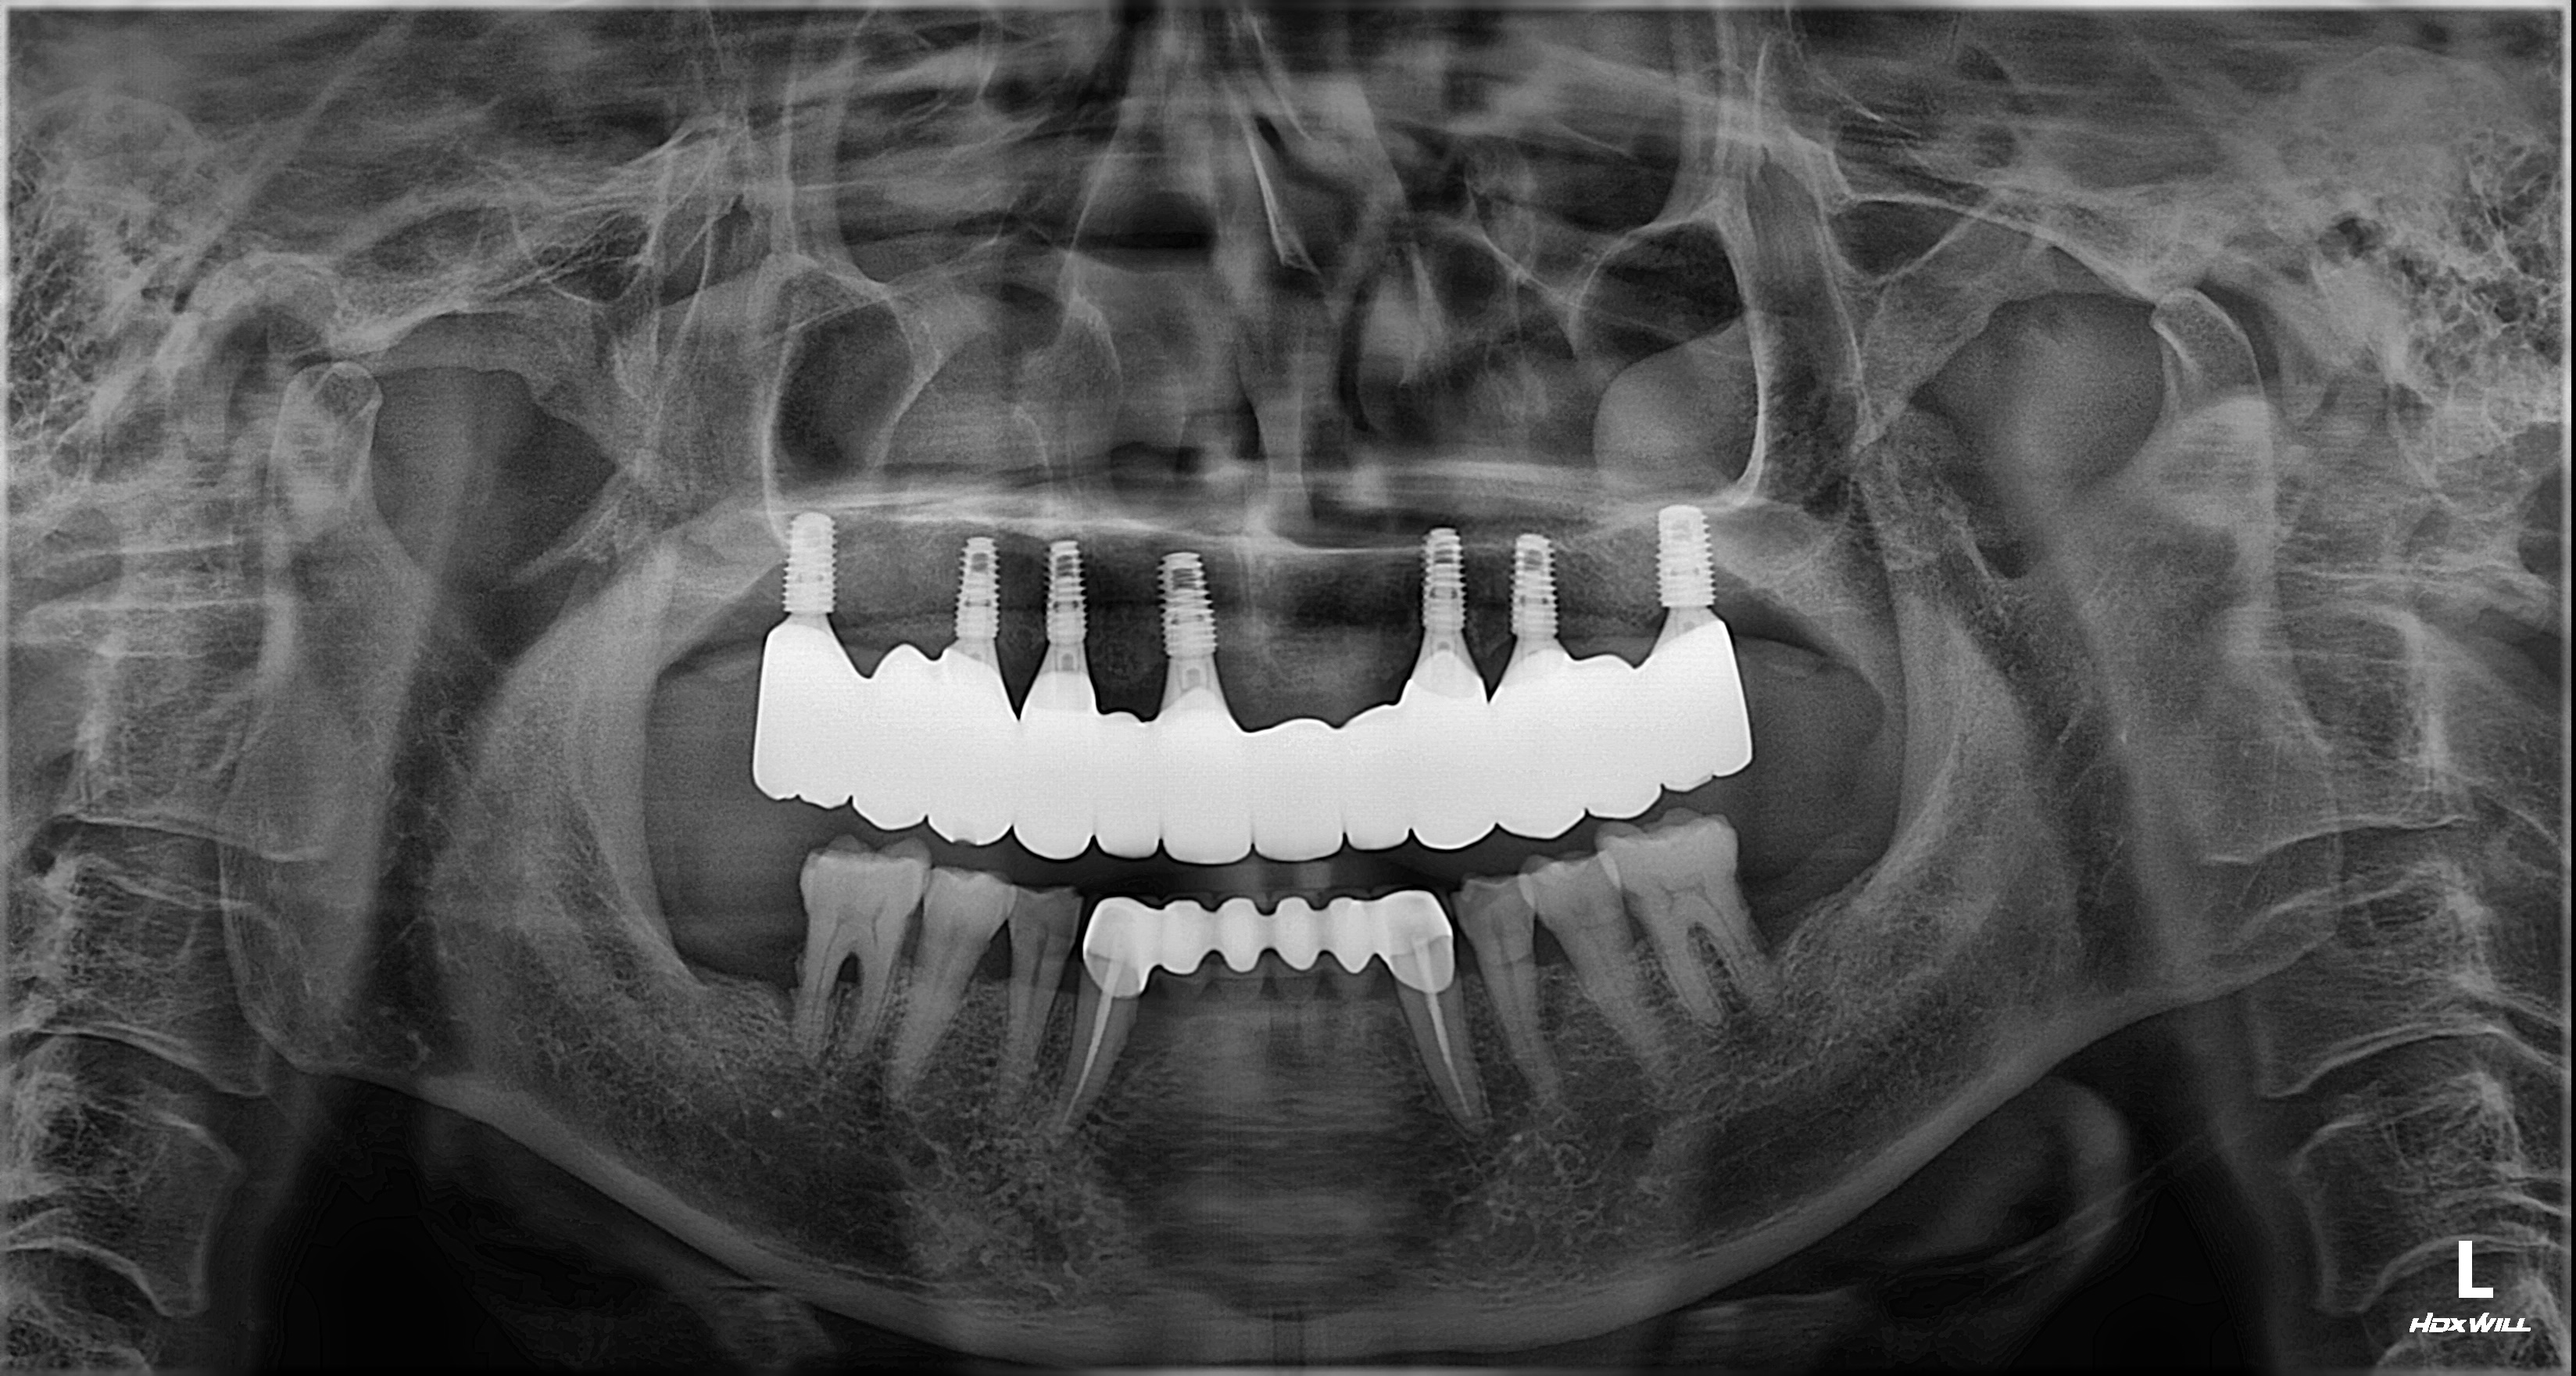

촬영일시: 2026.03.10. [ 치료기간: 2025년 09월 20일 ~2026년 02월 21일 ] ※ 365서울앞선치과의원의 모든 컬럼은 각 진료과 의료진이 직접 작성합니다. 365서울앞선치과의원 임상 케이스 게시물은 환자분께 의학적으로 정확하고 상세한 정보를 드리기 위해 각 진료과 의료진이 직접 작성하며, 모든 증례 사진은 본원 의료진이 직접 시술한 증례를 촬영한 것으로, 의료법 제23조, 제56조에 의거하며 환자분의 동의를 얻어 포스팅에 사용하였습니다. 또한 해당 케이스는 본 환자분의 치료 결과이며, 환자 상태에 따라 치료의 결과는 달라질 수 있습니다. |